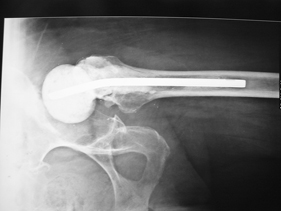

Department of Adult Joint Reconstructive Surgery

rivision total hip replacement for dislocation and severe bone defect

(pre-op) rivision total hip replacement for dislocation and severe bone defect

anterior-posterior view of left hip

lateral view of left hip